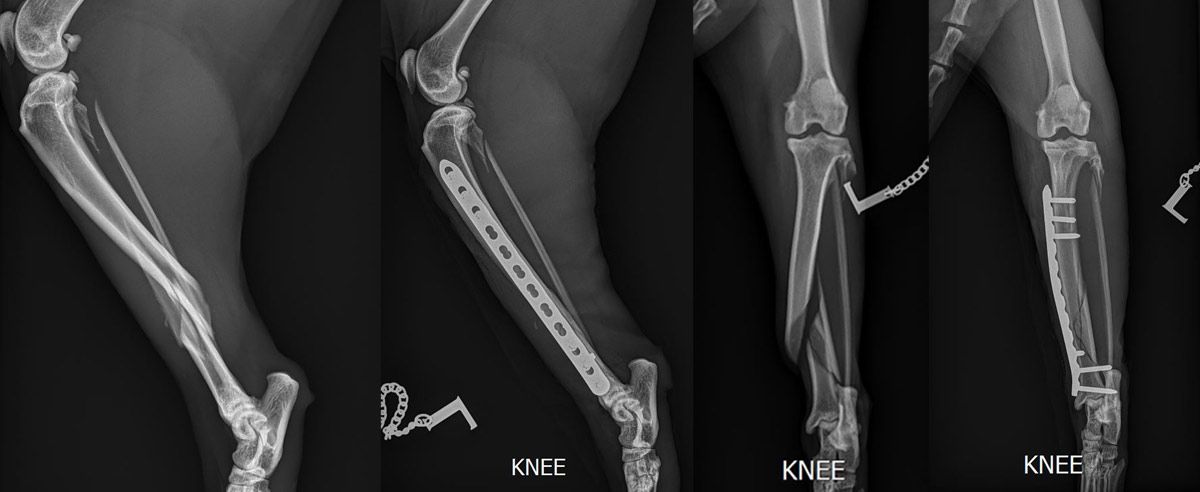

- Bildgebende Verfahren

• Röntgenaufnahmen